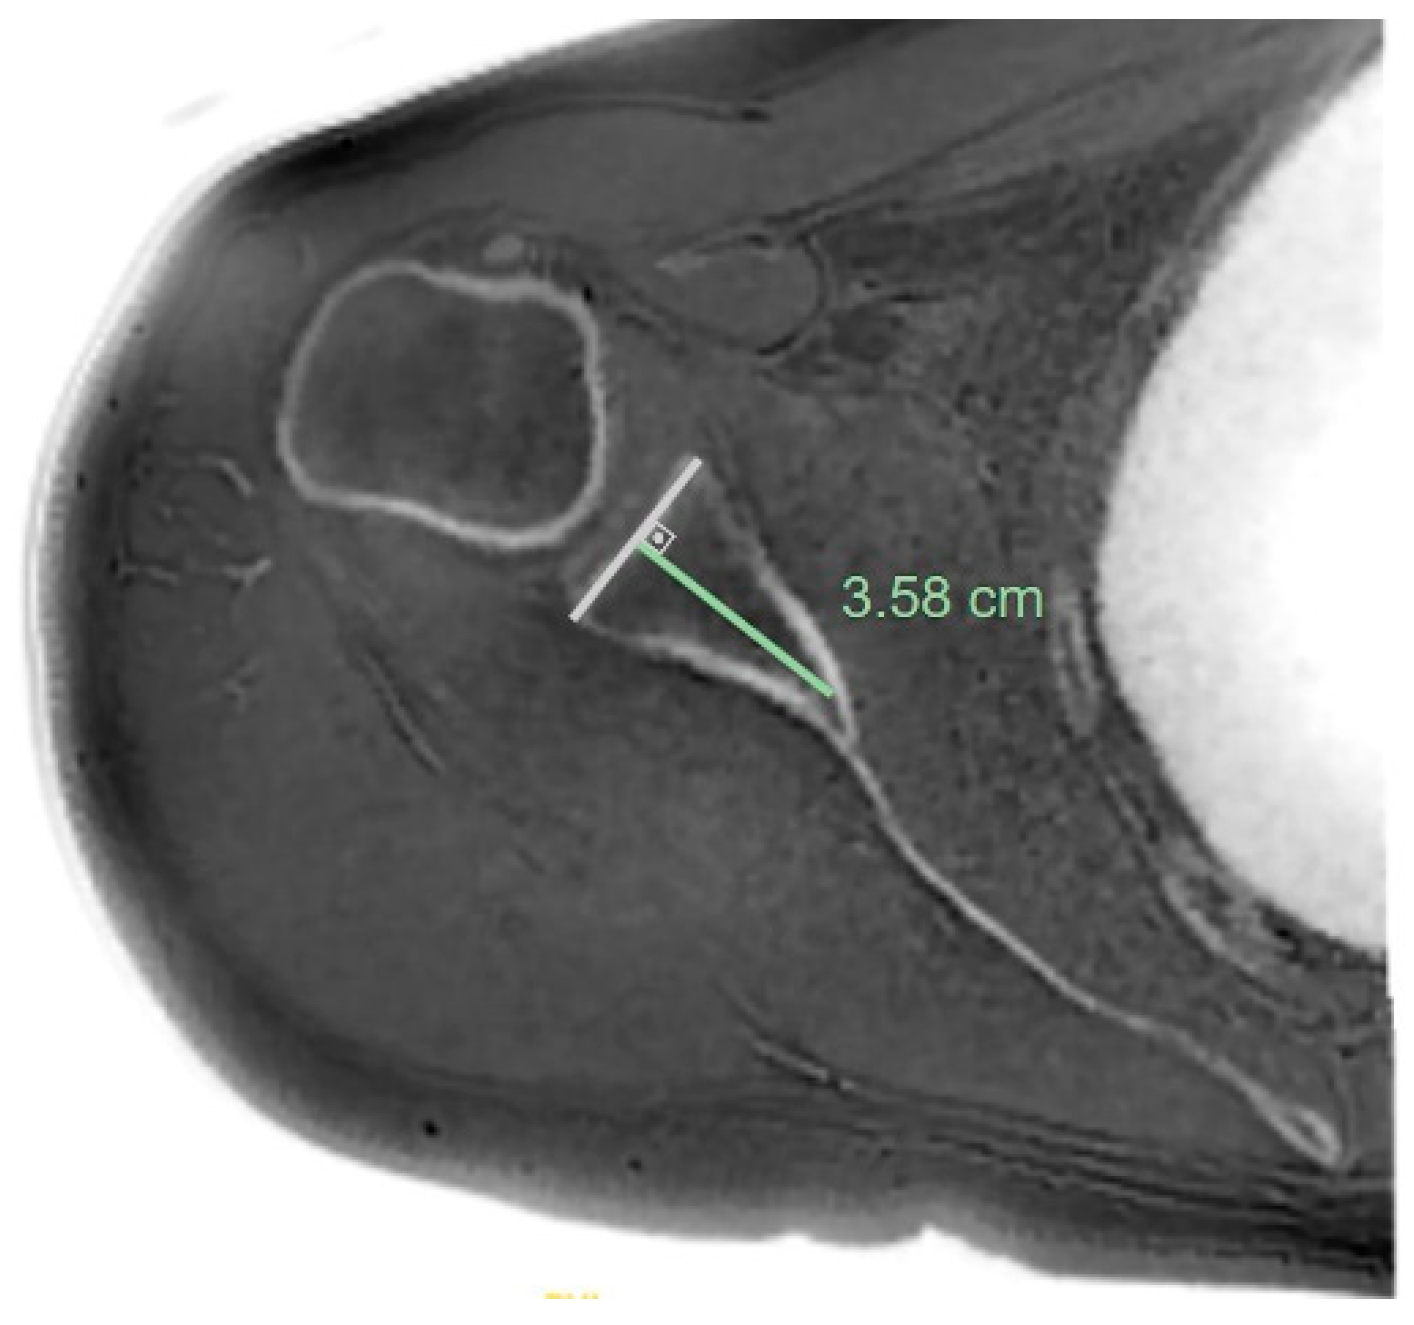

- MRI-based measurements